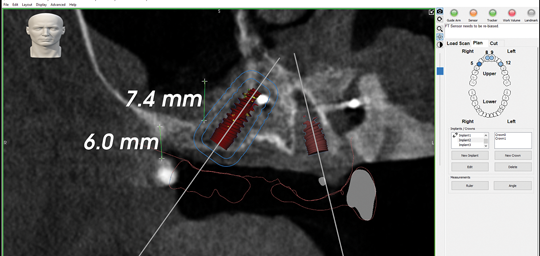

The all-digital treatment plan was prosthetically driven (Figure 2), with the clinician mindful of the critical urgency for optimal implant placement, with implants ideally 3 mm apart with most of the interproximal osseous crest maintained9 and with strict adherence to the design of the plan, based on Tarnow et al's esthetic guidelines for the maxillary anterior esthetic zone.10 The clinical team elected to use robotic guidance (Yomi® Dental Robotic System, Neocis, neocis.com), which on the day of surgery permits fiducial markers to verify the accuracy of placement, angulation, and depth.

Fig 2. Prosthetically driven digital treatment plan.

Figure 2

Fig 10. Maxillary and mandibular STL files of presurgical scans with proposed implant positions embedded into the files in design software, enabling design and milling of the provisional prostheses.

Figure 10